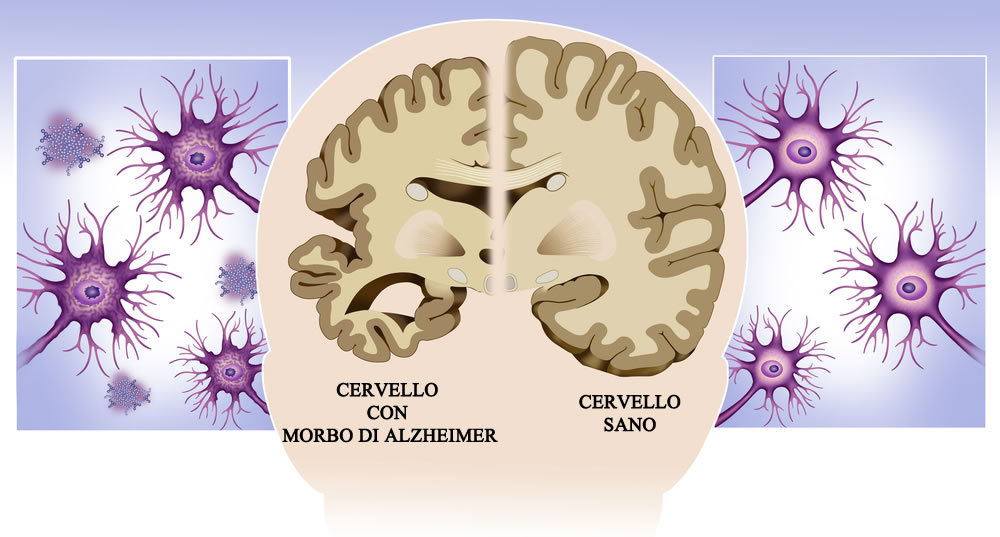

L’aumento dell’età è il principale fattore di rischio per il morbo di Alzheimer, una malattia neurodegenerativa progressiva che colpisce 5 milioni di persone negli Stati Uniti e circa 50 milioni a livello globale. Con il crescente invecchiamento della popolazione, i progetti di controllo e prevenzione dei centri per il morbo di Alzheimer raggiungeranno quasi il triplo entro il 2060.

Con l’invecchiamento, molti processi biologici son o disfunzionali e sono anche stati implicati nella malattia di Alzheimer. Ad esempio, mentre le persone invecchiano, hanno maggiori probabilità di avere un’infiammazione sistemica cronica e neuroinfiammazione che è associata a una funzione cognitiva peggiore. Altri malfunzionamenti dell’invecchiamento includono compromissione della clearance di proteine tossiche errate, disfunzioni mitocondriali e metaboliche (associate al diabete), problemi vascolari, cambiamenti epigenetici (cambiamenti nella regolazione genica senza alterazioni nella sequenza del DNA) e perdita di sinapsi (punti di comunicazione tra neuroni).

Gli studi di fase successiva (fase 3) sono dominati dai farmaci che prendono di mira la proteina beta-amiloide e la tau, le classiche caratteristiche patologiche del morbo di Alzheimer (degli studi di fase 3, il 52% si rivolgono all’amiloide o alla tau), ma altre strategie stanno guadagnando terreno e sono in fase 1 o 2, secondo il documento di revisione.